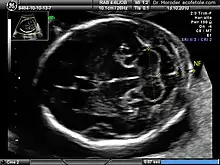

![]() Measurements of fetal nuchal translucency, nasal bone and facial angle according to the standards of the Fetal Medicine Foundation | |

Nuchal scan (NT procedure) is performed between 11 and 14 weeks of gestation, because the accuracy is best in this period. The scan is obtained with the fetus in sagittal section and a neutral position of the fetal head (neither hyperflexed nor extended, either of which can influence the nuchal translucency thickness). The fetal image is enlarged to fill 75% of the screen, and the maximum thickness is measured, from leading edge to leading edge. It is important to distinguish the nuchal lucency from the underlying amniotic membrane.[8]

Normal thickness depends on the crown-rump length (CRL) of the fetus. Among those fetuses whose nuchal translucency exceeds the normal values, there is a relatively high risk of significant abnormality.